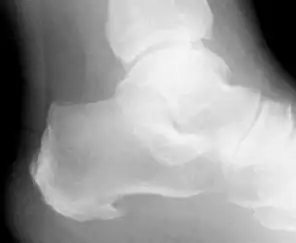

![]() Radiografía que muestra un espolón calcáneo inferior. | ||

El espolón calcáneo fue descrito por Jean Leliévre[1] a mediado del siglo XX, que describió la aparición de cristales de ácido úrico en forma de espuelas que invadían a la fascia plantar, pero solamente se evidenciaba al realizar la cirugía. Se usa erróneamente para referirse a la cicatrización de varios fascículos de la inserción de la fascia plantar en el calcáneo, que al cicatrizar lo hace con depósito cálcico en forma de hueso ,dando la imagen de espuela. Esta es una osificación heterotópica de dicha fascia plantar. Muchas veces es asociado con el dolor en el talón del pie, siendo en la mayoría de las veces una fascitis plantar o inflamación de la inserción de la fascia plantar, lo que lleva como consecuencia a la inflamación de las celdillas de la almohadilla calcánea, produciendo dolor sobre todo al levantarse o incorporarse después de estar sentado.

El diagnóstico de espolón calcáneo es la aparición del síntoma junto a la elevación de niveles de ácido úrico en la sangre lo cual está altamente correlacionado con el subyaceente proceso de calcificación.[2] La sola aparición radiográfica de la osificación heterotópica en el calcáneo, es solamente el estigma de cicatrización de la fascia plantar en forma de hueso, la cual puede ser muchas veces indolora.